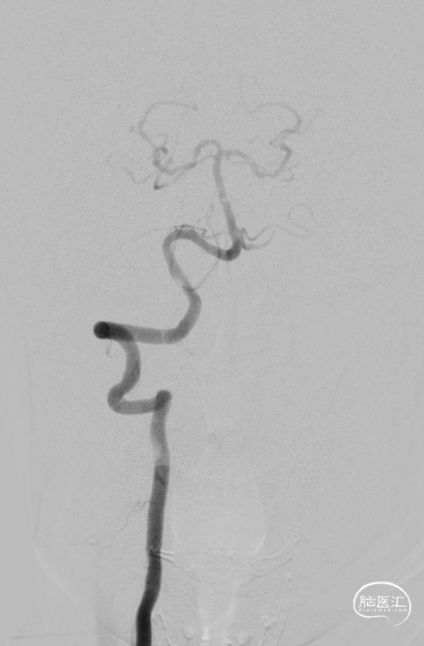

全脑血管造影DSA:双侧椎动脉起始段狭窄。远端供血不足。

患者双侧椎动脉均狭窄,左侧重度狭窄。左侧椎动脉充盈延迟、血流瘀滞,为闭塞前表现。所以权衡双侧椎动脉狭窄血管成型术的指征,优先处理左侧椎动脉起始段狭窄。为预防急性后循环缺血性卒中,在家属知情同意前提下行支架成形术。

沿微导丝送入2.5mm*15mm球囊预扩张狭窄处。